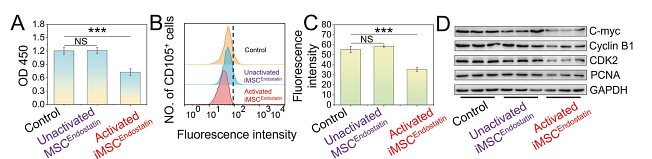

发表文章中的应用

| WB | 查看 22 篇文献如下 |

| Co-IP | 查看 1 篇文献如下 |

| IF | 查看 1 篇文献如下 |

Intelligent drugs based on notch protein remodeling: a defensive targeting strategy for tumor therapy

Author: Sun Yuliang,et al

PMID: 39198434

期刊: Cell Death & Disease

应用: WB

反应种属: Human

发表时间: 2024 Sep

-